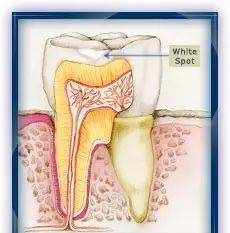

白斑

牙垢沉积在牙齿表面,牙齿表面珐琅质被牙垢中的细菌消化糖后,排泄出来的酸溶解,就发生脱矿了。

牙齿中的钙减少了,色泽就变成白粉笔色(白琧)感觉了。

牙齿的早期龋齿(白斑时期),可以通过日常使用含氟牙膏、护牙素,定期看牙医进行涂氟来进行修复。